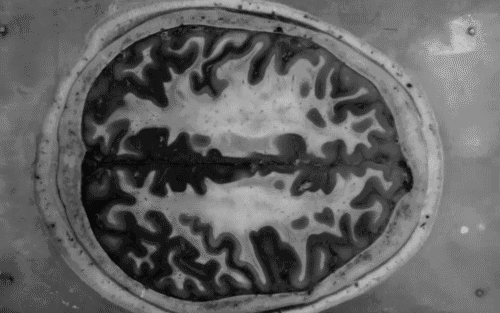

Nova metoda koja daje odgovor na jednu od najvećih životnih zagonetki

Nesrazmjer između moždane starosti i vaših stvarnih godina indikator je budućih problema kognitivnog i tjelesnog zdravlja.

Britanski znanstvenici složili su računalo koje će donijeti odgovor na jednu od najvećih životnih zagonetki - kada ćemo umrijeti? Stručnjaci s Imperial Collegea u Londonu razvili su metodu prepoznavanja stanja i volumena moždanog tkiva koje će ljudima odrediti moždanu starost i iz toga izvući niz bitnih zaključaka o zdravlju i životu pojedine osobe.

Testiranje na starijim sudionicima istraživanja pokazalo da što je veća razlika između moždane starosti i stvarne dobi, veće su šanse da će doći do pogoršanja mentalnog i tjelesnog zdravlja te do rane smrti.

Ova tehnika, iako je još na klimavim nogama, s vremenom će jednostavnom magnetnom rezonancom pomoći otkriti tko je u opasnosti od pada kognitivnih funkcija i smrti prije 80. godine života.

'Otići ćete liječniku, napraviti sken mozga i on će vam reći - vaš mozak je 10 godina stariji no što bi trebao biti - te će vas savjetovati o promjenama koje trebate napraviti kako bi vam se stanje popravilo', kaže autor studije dr. James Cole.